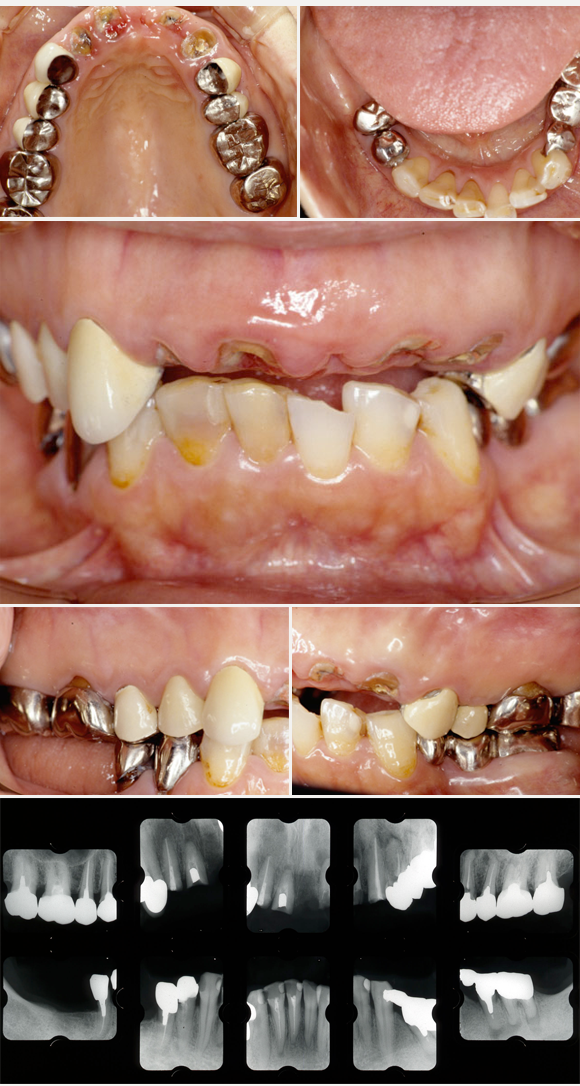

【審美歯科の治療事例】

上前歯の外傷で来院、多くの問題がありました